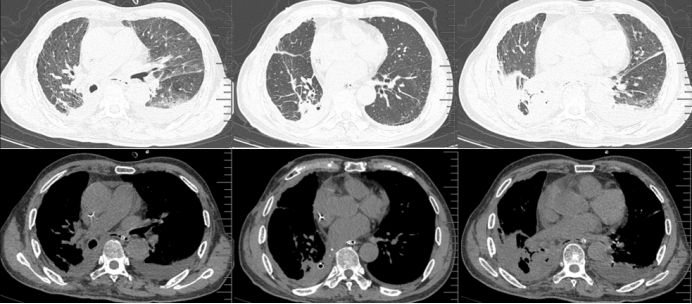

2024年7月21日胸部CT提示:右侧胸腔大量高密度影,中间有较多气体影像,部分肺组织受压不张,支气管胸膜瘘或食管胸膜瘘形成可能(图3)

图片

3  患者胸部CT(2024-07-21)

7月30复查胸部CT提示炎症吸收好转,肺复张较前明显(图4)将抗感染药物降阶梯为头孢哌酮舒巴坦,安置空肠管,启动肠内营养。

4  复查胸部CT(2024-07-30)